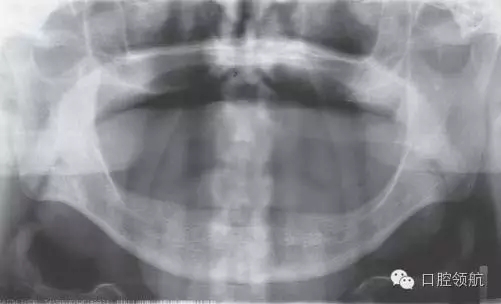

初診時(shí),口內(nèi)所見(jiàn)(圖1),曲面斷層片顯示(圖2),患者植入?yún)^(qū)骨量不足,前庭溝深度不足,附著齦的量不足。

圖2 初診時(shí)曲面斷層影像。

圖9 種植體植入3個(gè)月后曲面斷層影像。